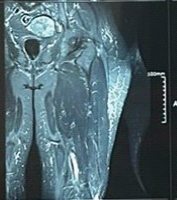

He underwent cervical posterior spinal fusion (C3/4) on the same day. Fig. 2 shows post-operative images. He was released from bed confinement with full assistance on post-operative day 2; however, he had severe ataxia and difficulty in standing with assistance. Therefore, VR rehabilitation using KAGURA, which can be performed in a sitting position with assistance, was started 1 week postoperatively. The use of KAGURA is presented in the figure (Fig. 3). Fig. 3a shows KAGURA being used by a physical therapist at our hospital, which differs not from actual patient use. The patient sat on a chair with a backrest and underwent rehabilitation. When significant trunk instability caused a risk of falling, a chair with armrests was used. One physical therapist attended, fitting a head-mounted display to the patient’s head and having them grip controllers in both hands (Fig. 3b). When gripping was difficult, the patient’s hand and controller were held with a belt, enabling them to grip the controller. There are five games built into KAGURA. In this case, two games were used: One was “a game for reaching out to targets,” and the other was “a game for catching balls falling from the sky,” both designed to be easily understood by elderly players (Fig. 3c and d). During periods of severe motor paralysis, the physical therapist assisted the patient while the game was being played. These interventions were carried out for 20–30 min/day, 2–3 times/week, depending on the patient’s condition.

Figure 2: Post-operative X-ray image of the cervical spine. C3/4 was fixed using a pedicle screw, and stability was achieved. (a) Anteroposterior view of the cervical spine. (b) lateral view of the cervical spine.